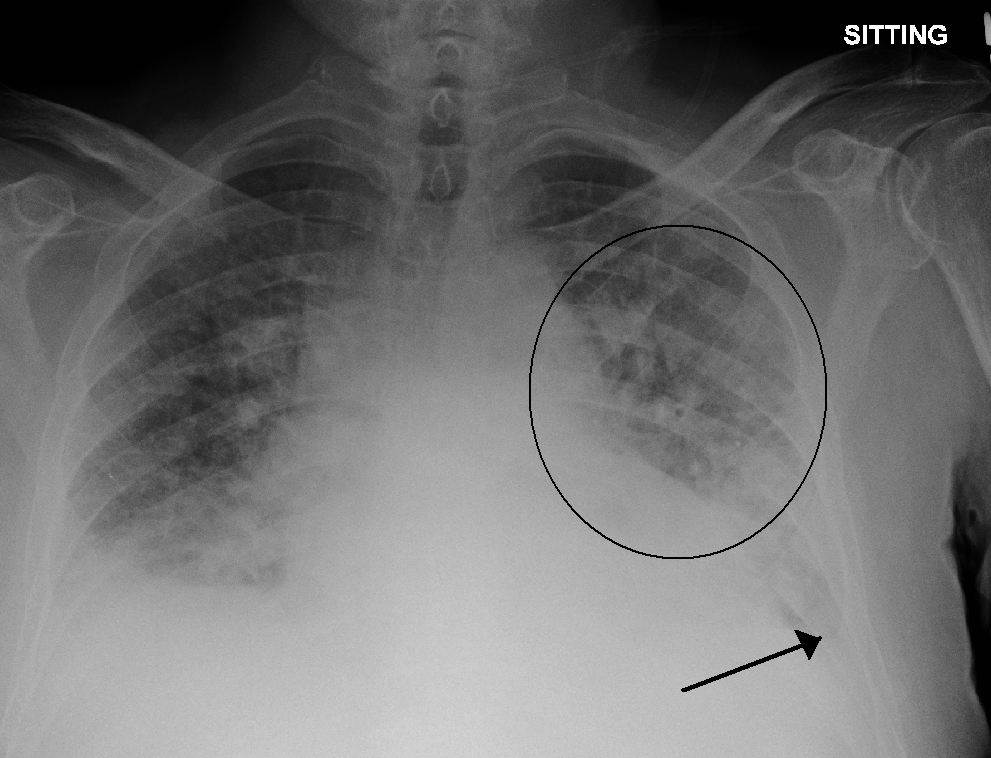

Apa yang dimaksud dengan Edema Paru atau Pulmonary Edema? - Ilmu Kedokteran - Dictio Community

Edema paru - Wikipedia bahasa Indonesia, ensiklopedia bebas

Ketahui Perbedaan Edema Paru dan Efusi Pleura

Penyakit Edema Paru - Gejala, Penyebab, Pengobatan - Klikdokter.com

Edema Paru - Gejala, penyebab dan mengobati - Alodokter

Edema Paru: Penyebab, Gejala, dan Pengobatan | Hello Sehat